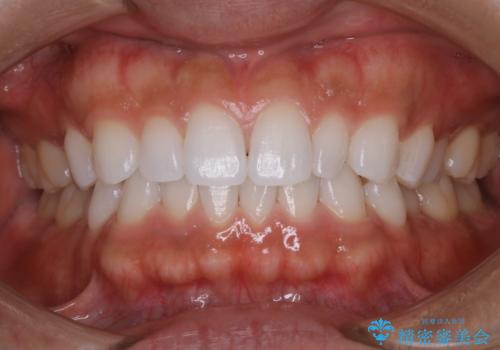

プラークが放置されると、そこで病原菌が繁殖し始めます。そうなるとバイオフィルム(歯面に強固に付着したばい菌の膜)になり、歯肉に炎症が生じ歯周病の引き金となります。

プラークやバイオフィルムといった細菌などを放置すると歯石となります。歯石になってしまうと歯磨きでは取り除くことができないため、歯科医院にて専門的な機械や材料を使用してクリーニングを受ける必要があります。

PMTCは審美的な面だけではなく、虫歯や歯周病予防にもなります。虫歯や歯周病予防のためには、お口の中を清潔に保つことが大切です。